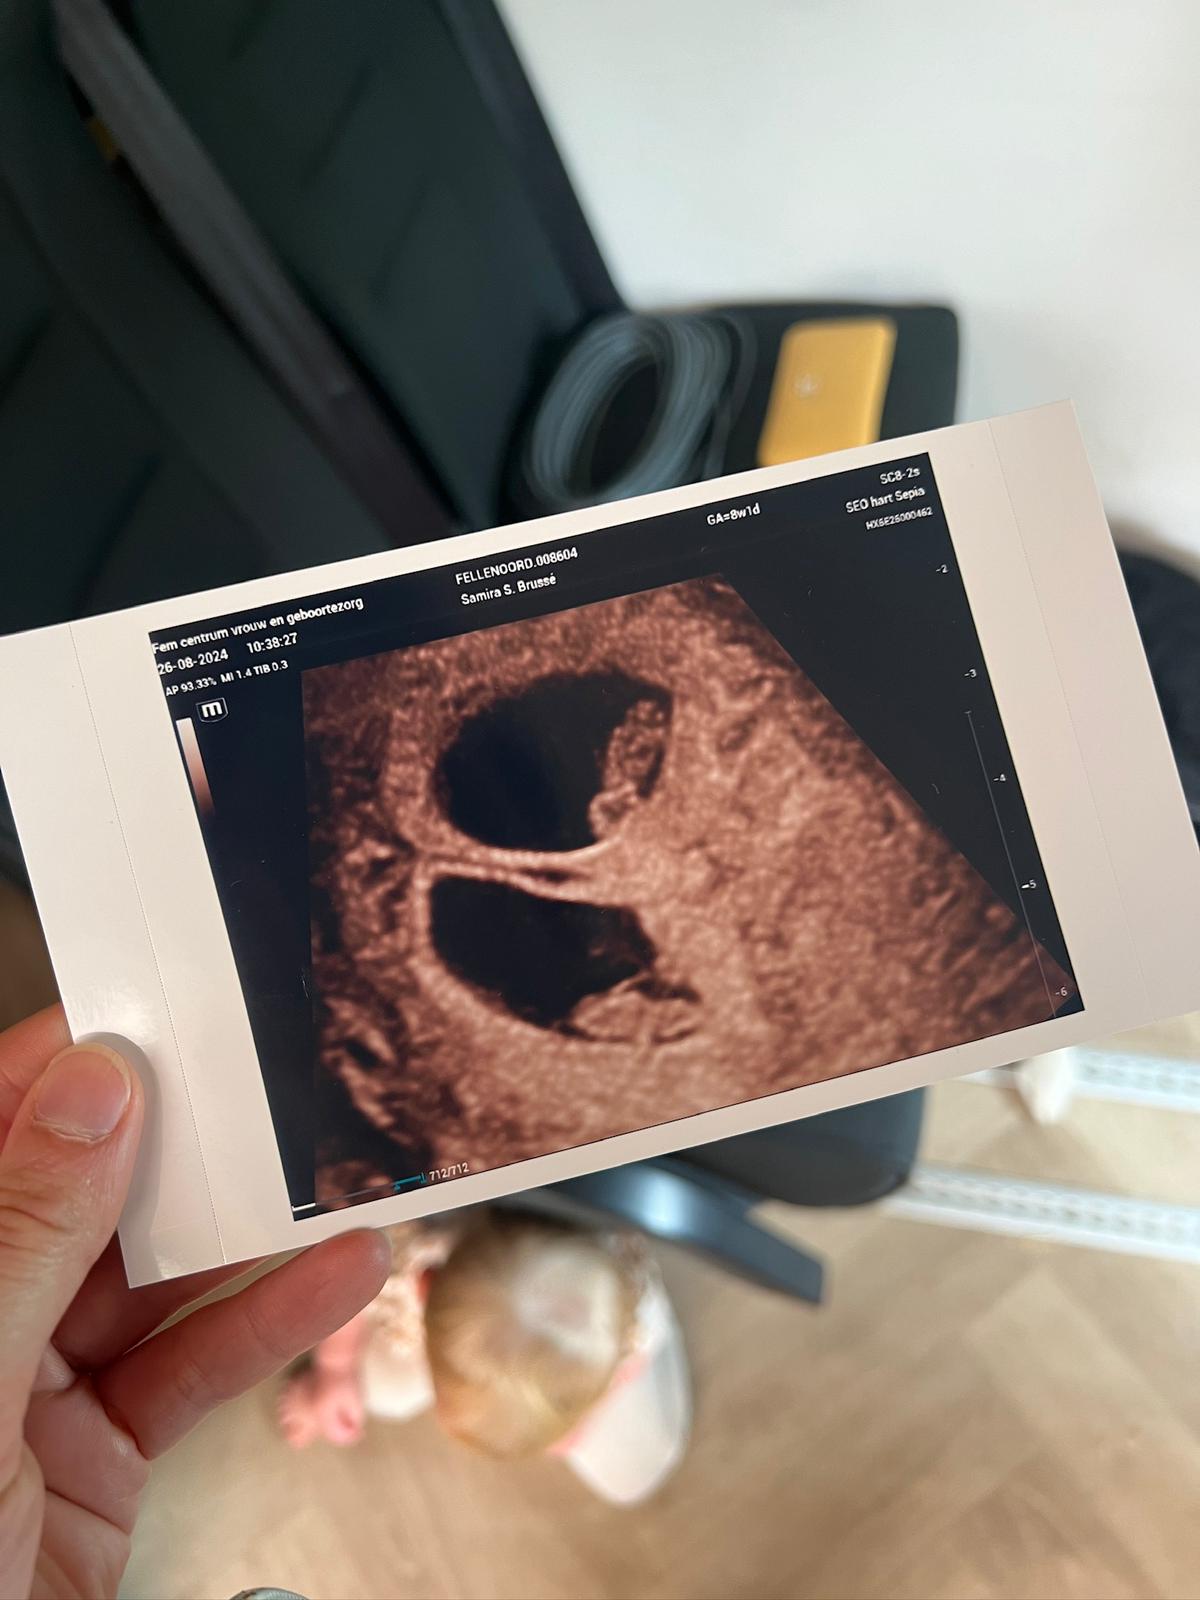

Echo van een tweeling

De eerste echo werd dan ook gepland

We gingen er heel relaxed heen, maar iets minder relaxed weg… Op de echo was namelijk meteen overduidelijk te zien dat er twee placenta’s waren met in beide een levend wezentje. *slik* We werden meteen doorverwezen naar de gynaecoloog in het ziekenhuis, want een tweeling is standaard een medische zwangerschap.